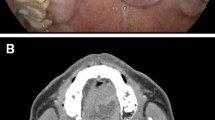

From April 2016 to May 2018, 102 patients with palatal tumors and intact mucosa, who presented with a similar chief complaint (Fig. 1), were enrolled in this study. All patients were treated at the Department of Oral and Maxillofacial-Head and Neck Oncology, Ninth People’s Hospital, Shanghai Jiao Tong University School of Medicine. This study was approved by the hospital ethics committee. Informed consent forms, which had been approved by the ethics committee and the institutional review board of the hospital, were obtained from all patients.